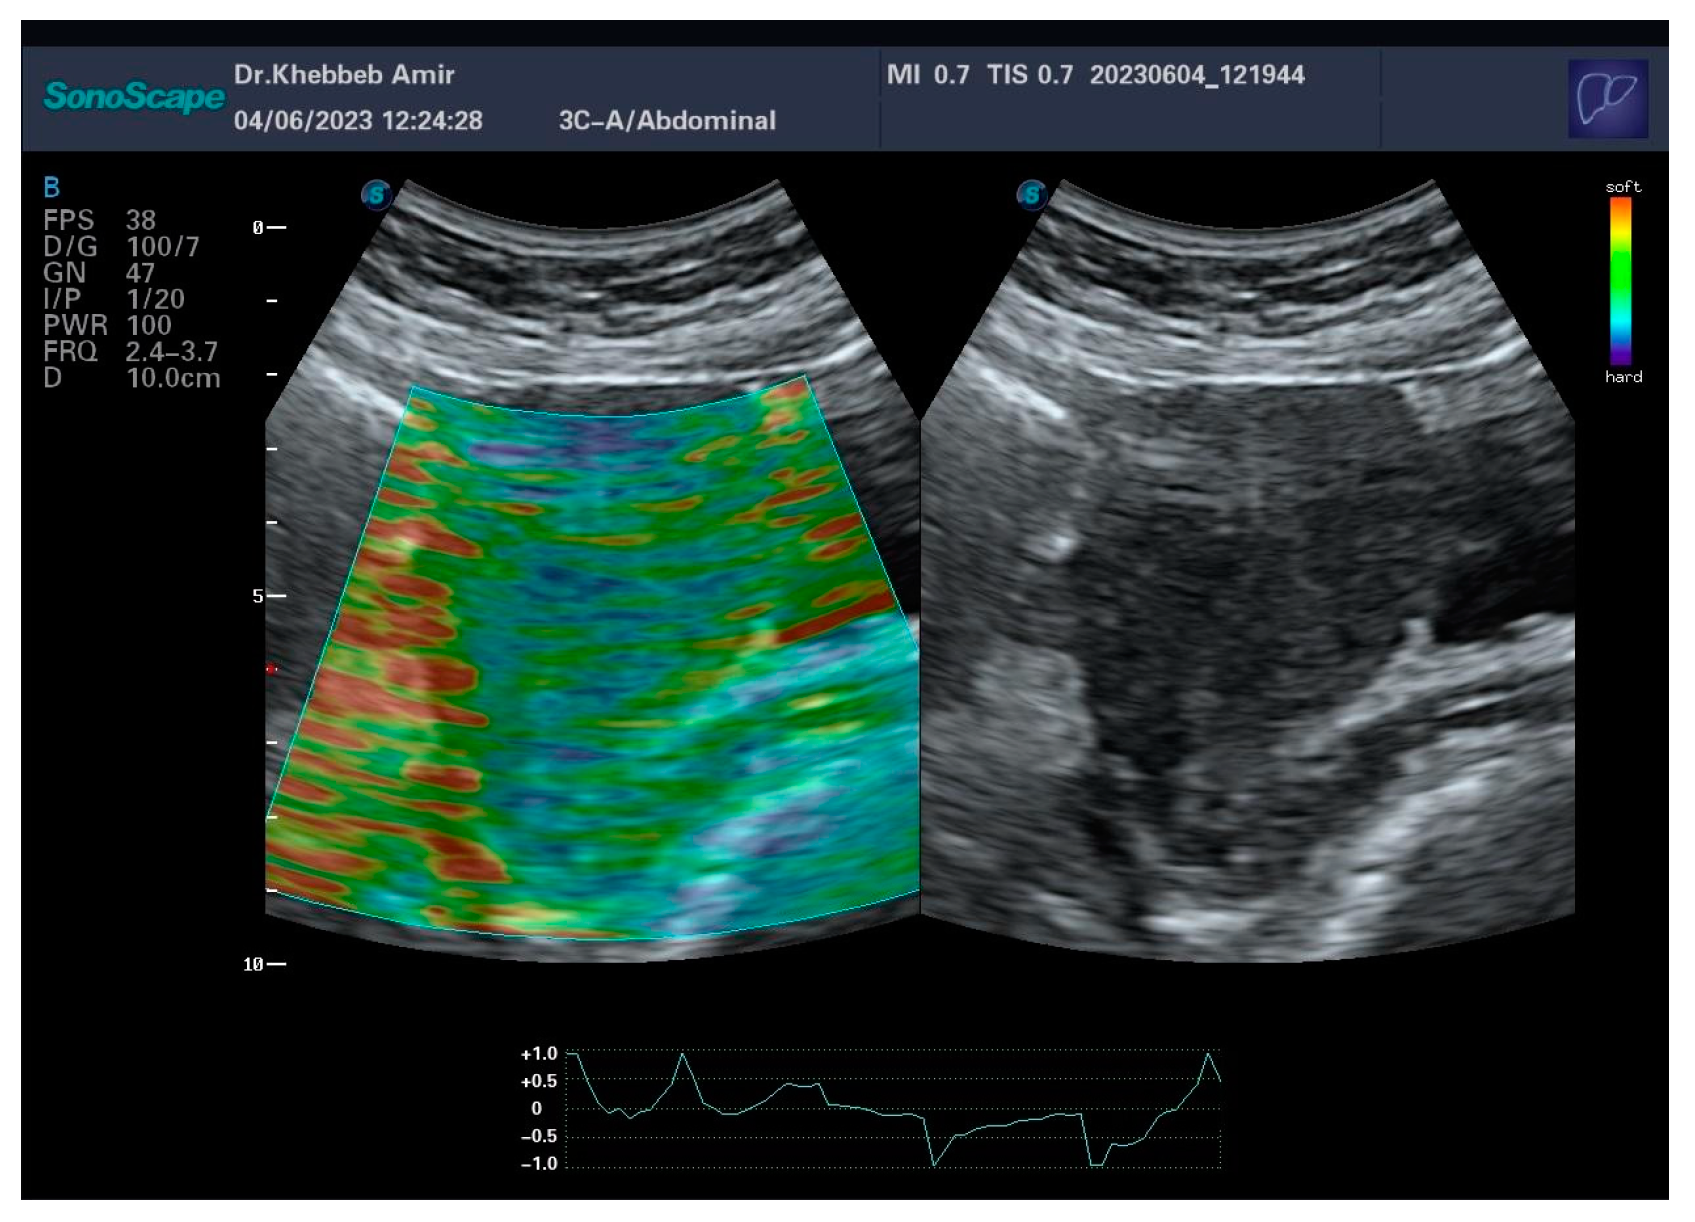

To gain further insight into the action of HH, we conducted elastography examinations before and after its administration.

Elastography is an emerging ultrasound imaging technique used to measure tissue elasticity and stiffness[6] . Although commonly used in hepatology and endocrinology, it is still relatively rare done in obstetrics and gynecology.

In the imagery, we can see a difference in the elasticity of the myometrium before and after the treatment:

Predominance of blue shades (Figure 4) before HH administration indicates stiffness of the uterus (retracted myometrium).

Green, yellow and even red shades in the uterus (Figure 5) obtained after HH administration indicates that there was a myorelaxation like described before. We can even notice a considerable attenuation of blue shades in the fundus. From these findings, we suggest that the uterine myometrial relaxation, from blue to red is actually responsible for follicular growth, the red shift nomenclature is a tribute to a cosmological phenomenon related to the observation of galaxies fading away due to the expansion of the universe.

Figure 4. Elastography exam, before Hedera Helix administration.

Figure 5. Elastography exam, two hours after Hedera Helix administration.